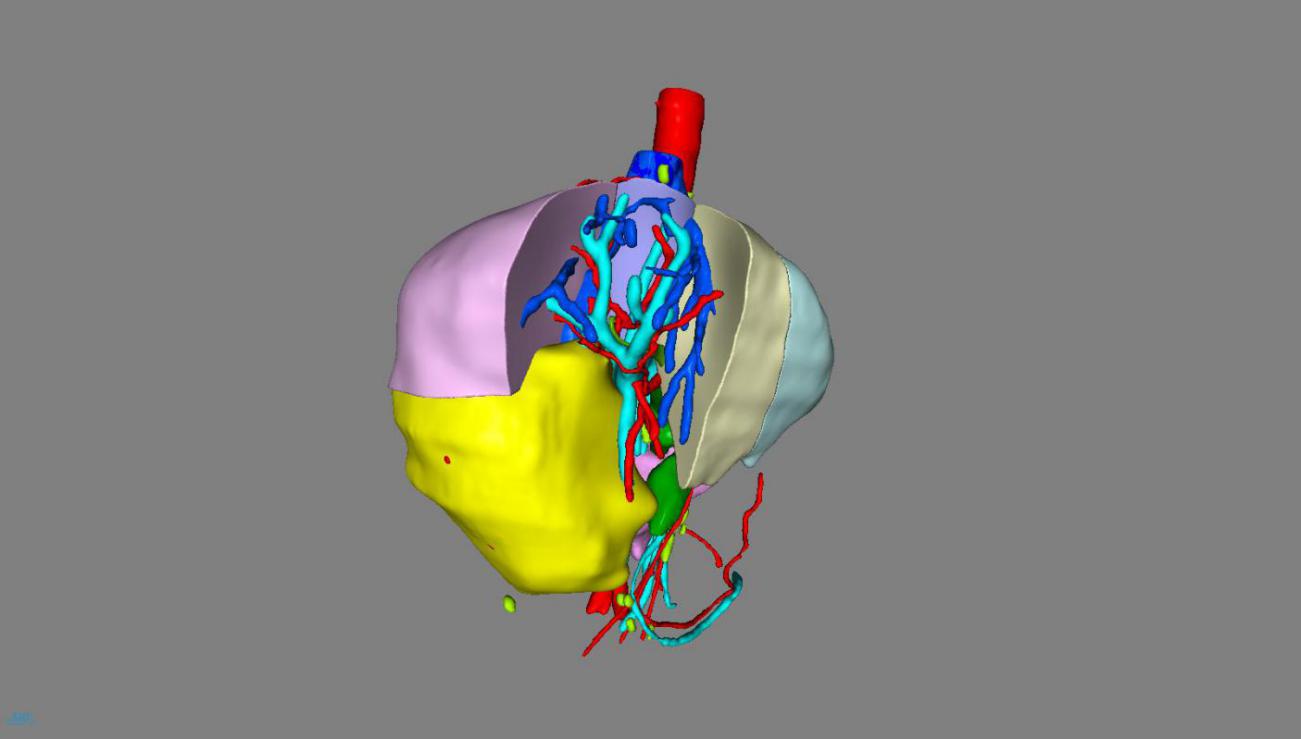

一、术前利用计算机3D模拟可视化技术测算肿瘤的体积和形态、癌栓的位置、血管的走行以及切除肿瘤后剩余肝脏的体积,制定了首选手术方案及备选手术方案;

李晓武 教授团队仔细阅读影像片后指出:肝脏恶性肿瘤手术既要保证肿瘤的根治切除,又需要保证手术切除后肝脏功能满足人体需要,手术、麻醉、术中出血、术后感染等对肝脏功能均有影响,此例患者肿瘤巨大,单是切除肿瘤已有很大难度;肿瘤与血管关系密切,术中出血也是个难题;切除后肝脏功能维持更是难点。需要术中精准切除、减少出血、尽量保留有功能肝脏及其功能血管,难度巨大。

经过周密的术前准备,2018年10月17日,肝胆外科李晓武教授团队给患者实施了精准右半肝切除术。术中探查结果与术前规划基本一致,整个手术历时2.5小时,术中釆用凝血器切肝,半肝血流阻断,切肝时间18分钟,切肝过程“0”出血,“0”输血,整个手术过程出血100ml。标本大小13*10cm,完美展现了精准肝切除、无血肝切除的理念。术后,患者生命体征平稳,清醒后送回普通病房。